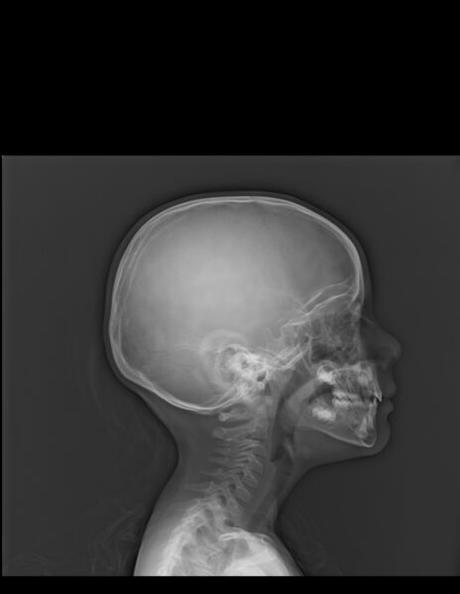

RADIOGRAFIA LATERAL DE CUELLO (VALORACIÓN AMÍGDALA)

HALLAZGOS:

-Tejidos blandos, con densidad y morfología respetada, sin evidencia de lesiones.

-Cuerpos vertebrales, central. Sin listesis. Lordosis cervical, con rectificación.

-En lo observado de senos paranasales y celdillas mastoideas con adecuada neumatización.

-Estructuras óseas observadas de cráneo sin evidencia de lesiones líticas, blásticas o perdida de la contigüidad.

-Espacio entre apófisis odontoides y C1, menor de 5 mm.

-Nasofaringe, adenoides, con un crecimiento aproximado mayor al 50% menor al 75%, dando una solución Grado 2.

OPINIÓN RADIOLÓGICA:

EL PRESENTE ESTUDIO RADIOGRAFICO CON HIPERTROFIA AMIGDALINA MODERADA (GRADO II).

CORRELACIONAR CON DATOS E HISTORIA CLINICA DEL PACIENTE.